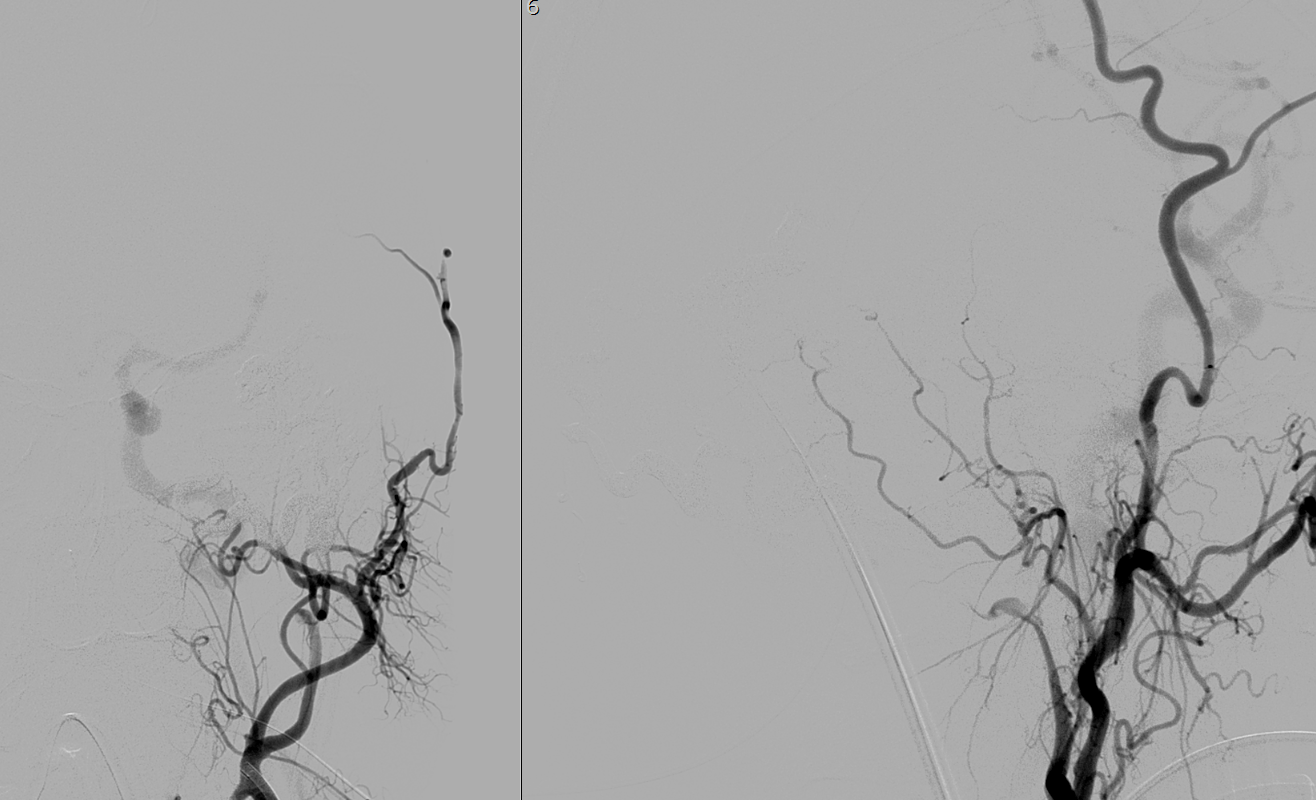

Se procede a realizar angioTC de troncos supraaórticos observando un drenaje venoso precoz de venas corticales temporales izquierdas y aumento de calibre de la arteria carótida externa izquierda, hallazgos compatibles con posible fístula dural (imagen 2).

Se realiza arteriografía a las 12 horas del ingreso que muestra fístula arteriovenosa dural con aferencias arteriales de arteria occipital izquierda y drenaje a vena cortical temporal izquierda. Compatible con fístula dural Cognard tipo IV.

Podemos ver la visión lateral y AP en la figura 3: